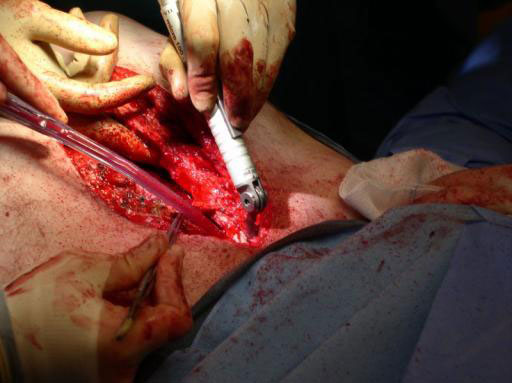

While many surgeons currently remove the sternum the new system allows for a procedure that involves reducing the sternal halves and implanting plates, which span the sternum and are fixed to the ribs and/or sternum of the patient. The chest wall is then reinforced through advancement of the pectoral muscles.

The Sternal Fixation System consists of titanium locking plates that function with 3.0 mm titanium locking screws, similar to those used in the mandible area. The straight plates are actually an assembly of two single plates, which are connected by a U shaped pin. In case of emergency removing the pin allows re-entry into the thoracic cavity. Long and straight plates are fixed to the ribs; additional smaller plates are available for fixation of the manubrium.

Sternal closure with Ti Plate system

Cases provided by J Thornton, UT Southwestern Medical Center, Dallas, TX